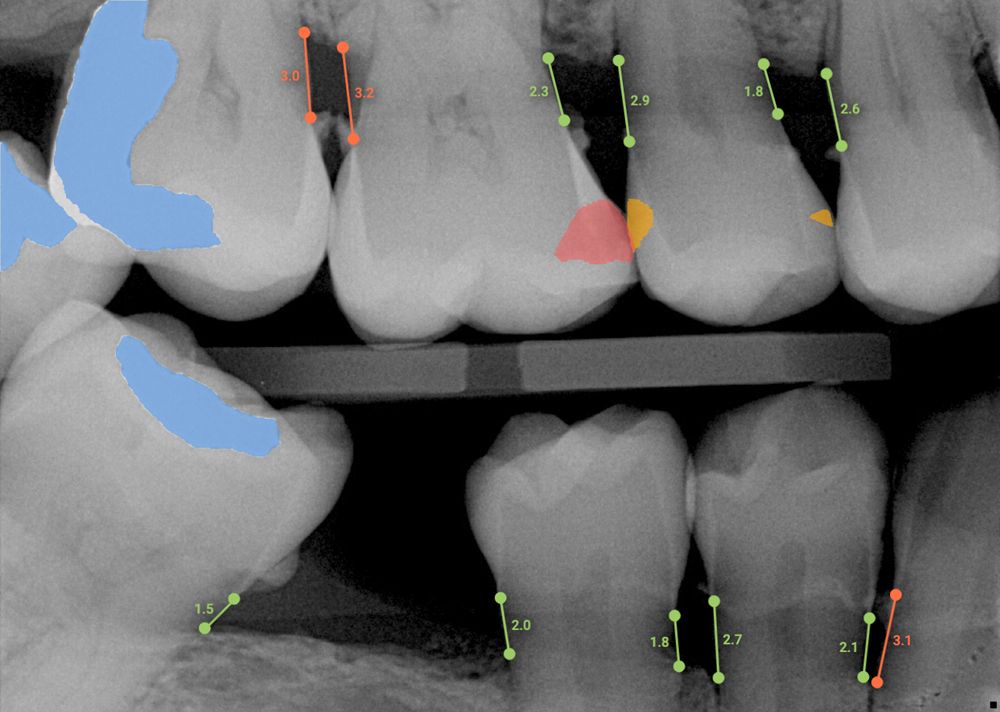

The AI technology analyzes and annotates x-rays in real time, adding a layer of data to the radiographs to help with clinical decision-making and patient education. Overjet is the only dental AI solution that is cleared by the United States Food and Drug Administration for bone-level quantification as well as decay and calculus detection. The data help dentists evaluate periodontal and restorative treatment needs.

Dr Gulati adds: “Many of our patients can’t conceptualize their condition. Then we pull up the x-rays and they see where Overjet has outlined cavities and displayed significant bone loss in red. People understand that red means something is not right. Their eyes are drawn to the monitor, and it helps them to codiagnose. They want to know the details. It’s a great communication tool.”

This image shows a radiograph with Overjet’s AI annotation.